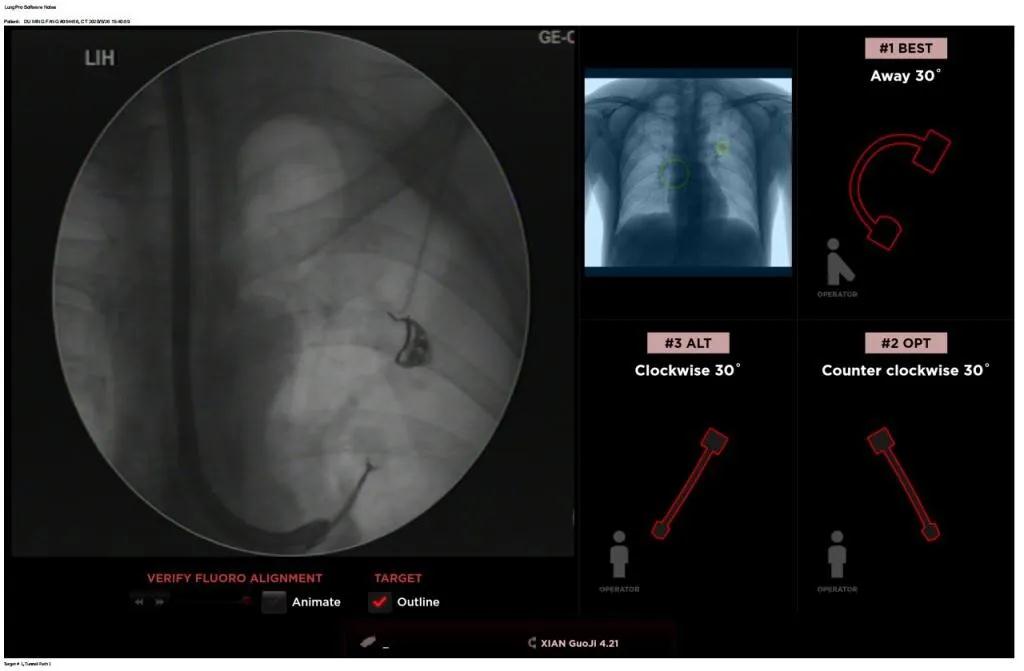

西安國(guó)際醫(yī)學(xué)中心醫(yī)院呼吸內(nèi)科完成西北地區(qū)首例LungPro全肺導(dǎo)航系統(tǒng)引導(dǎo)下BTPNA手術(shù)

近日,西安國(guó)際醫(yī)學(xué)中心醫(yī)院胸科醫(yī)院歐陽(yáng)海峰副院長(zhǎng)完成西北地區(qū)首例LungPro全肺導(dǎo)航系統(tǒng)引導(dǎo)下經(jīng)支氣管鏡跨肺實(shí)質(zhì)肺外周結(jié)節(jié)活檢術(shù)。

經(jīng)過(guò)充分的討論后,歐陽(yáng)海峰副院長(zhǎng)決定為患者實(shí)施LungPro全肺導(dǎo)航系統(tǒng)引導(dǎo)的經(jīng)支氣管跨肺實(shí)質(zhì)肺外周結(jié)節(jié)活檢術(shù)。Broncus導(dǎo)航系統(tǒng)LungPro具有全球領(lǐng)先獨(dú)創(chuàng)的BTPNA技術(shù)(支氣管鏡下跨結(jié)節(jié)抵達(dá)術(shù)),可以實(shí)現(xiàn)對(duì)氣道外周孤立性肺小結(jié)節(jié)的精準(zhǔn)定位,建立直接通往氣道外病變部位的通道,以實(shí)現(xiàn)全肺的診斷及后續(xù)治療。這項(xiàng)技術(shù)不僅彌補(bǔ)了現(xiàn)有支氣管鏡技術(shù)由于受限于病變部位是否有氣道可通向以及無(wú)法準(zhǔn)確定位病變部位而造成的較低診斷率,同時(shí)還彌補(bǔ)了CT引導(dǎo)下經(jīng)胸穿刺(TTNA)無(wú)法適用于某些特定部位如中央及肩胛骨等結(jié)節(jié)的問(wèn)題,并且還避免了經(jīng)胸穿刺給患者帶來(lái)氣胸、出血的高風(fēng)險(xiǎn),可有效提高肺部結(jié)節(jié)及早期肺癌診斷陽(yáng)性率,亦可用于早期肺癌的射頻消融或微波治療,具有微創(chuàng)、安全、同期雙肺診療等優(yōu)勢(shì)。

BTPNA技術(shù)整合了虛擬導(dǎo)航支氣管鏡VBN、氣道內(nèi)超聲r(shí)EBUS、TBNA、高壓球囊擴(kuò)張、X線(xiàn)輔助等多項(xiàng)三、四級(jí)呼吸內(nèi)鏡技術(shù)。歐陽(yáng)海峰副院長(zhǎng)有3000 TBNA、1000 rEBUS、500 VBN、800 球囊擴(kuò)張方面的技術(shù)積累,10年來(lái)個(gè)人每年完成三、四級(jí)呼吸內(nèi)鏡手術(shù)1200余例,這有效保障了BTPNA技術(shù)的順利開(kāi)展。

團(tuán)隊(duì)術(shù)前進(jìn)行了精心的準(zhǔn)備,通過(guò)高分辨率CT建立了導(dǎo)航路徑,在麻醉科手術(shù)室的配合下,借助LungPro引導(dǎo)順利的確定了病灶部位、建立隧道并實(shí)施活檢,術(shù)后患者恢復(fù)順利出院。